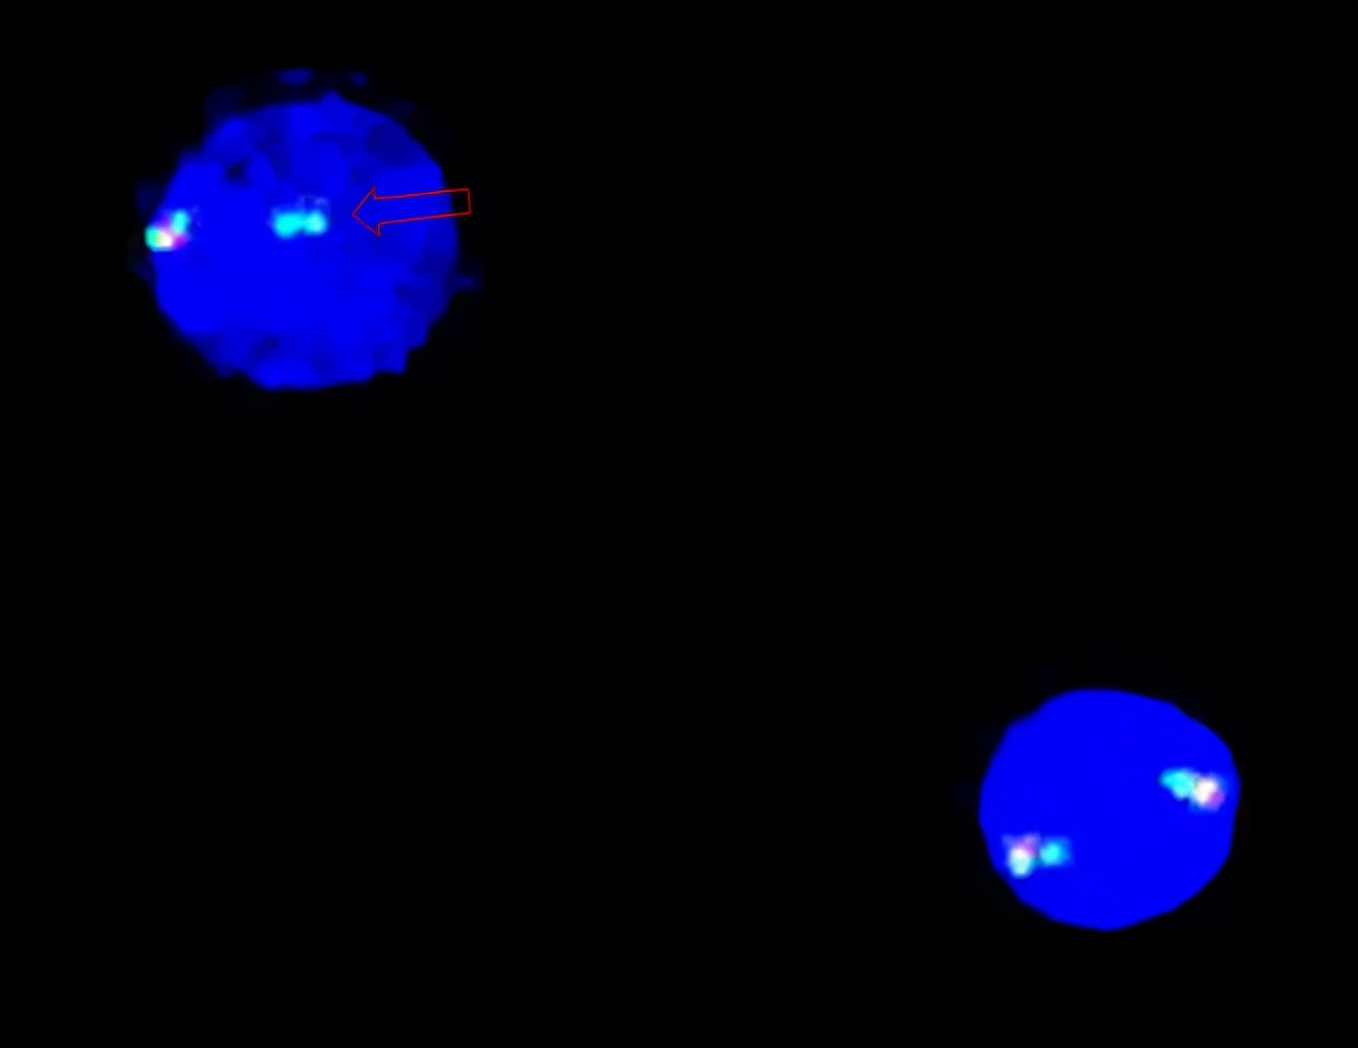

完善骨髓穿刺活检 ,骨髓涂片发现:有核细胞增生明显活跃, 嗜酸性粒细胞比例明显升高,为37.5%,以成熟嗜酸性粒细胞为主 ,中、晚幼嗜酸性粒细胞中有嗜碱性颗粒,部分细胞有空泡变性;外周血涂片嗜酸粒细胞比例明显升高达60%。骨髓活检:骨髓增生活跃,嗜酸性中、晚幼粒细胞明显增多。 FIP1L1/PDGFRα融合基因阳性 (图2)。

图2:荧光原位杂交(FISH)分析:红色箭头所指为CHIC2区域的缺失,表明存在这种特异性缺失会导致4号染色体的其中一条存在FIP1L1-PDGFRα融合基因阳性